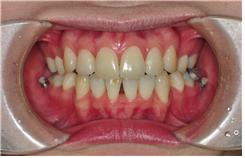

상악 잇몸들이 교정 시작부터 내려앉아 있는 상태였습니다.

활짝 웃을 때 잇몸이 너무 많이 보이는 것도 좋지 않지만,

잇몸이 아예 안 보이는 것도 좋지 않는 것이죠~

그래서 원장선생님께서 앞니를 들어올리도록 와이어에 장치같은 것을 만들어 주셔서

장착해주신 상태입니다~ 이번 월치료에 선생님께서 확인하시더니 앞니가 많이 올라갓다고

하셨어요~ 조금만 더 올라가도록 하자고 하시고 와이어교체하였습니다~